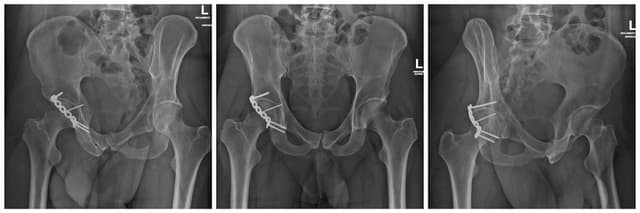

Posterior Wall Acetabulum ORIF

Pre-op

Post-op